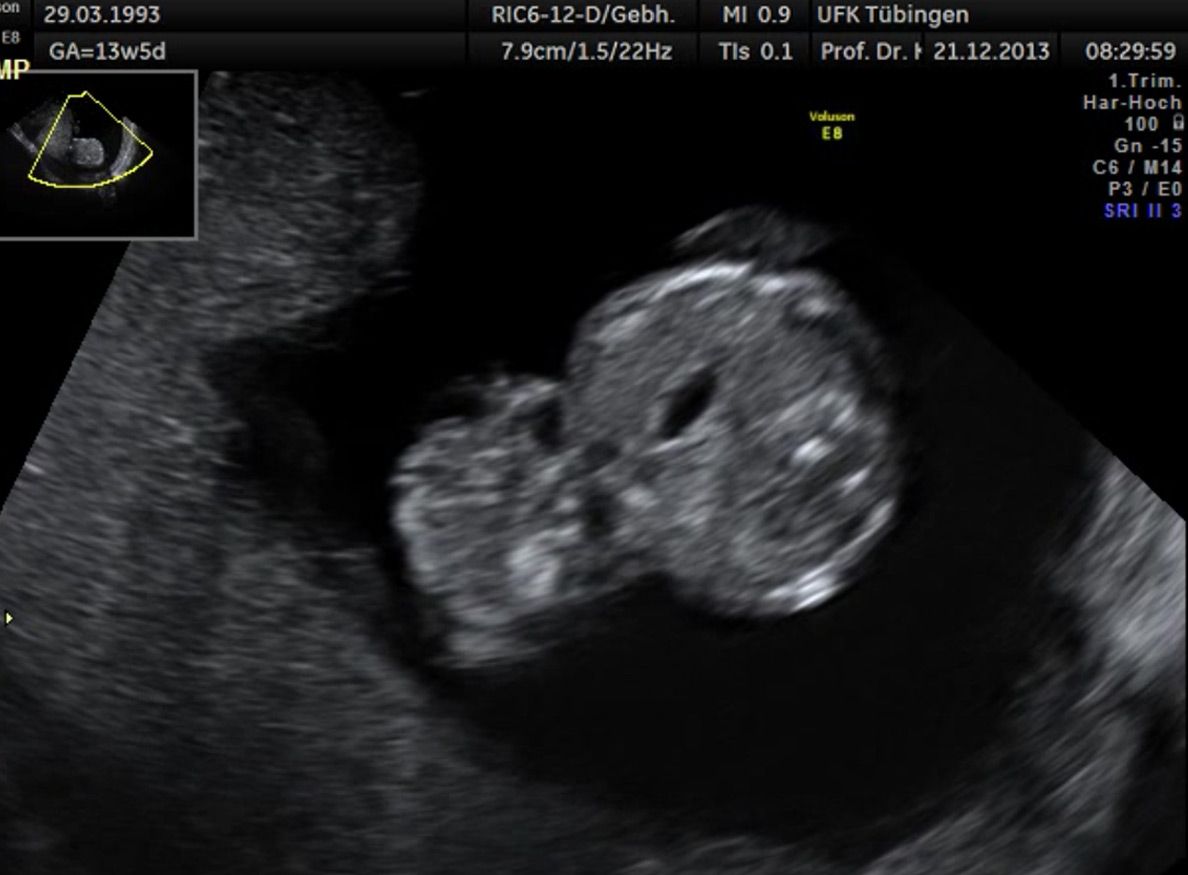

Im Rahmen des Ersttrimester-Screenings untersuchen wir die Organe des Feten mittels Ultraschall. Dabei machen wir auch gerne ein Bild für Sie.

Obwohl der Fet zu diesem Zeitpunkt erst zwischen 5 und 8cm groß ist, lassen sich bereits etwa die Hälfte aller schwerwiegenden Fehlbildungen erkennen bzw. ausschließen. Sollten wir eine Auffälligkeit sehen, werden wir mit Ihnen den Befund und das weitere Vorgehen ausführlich besprechen.

Die eigentliche Organuntersuchung findet um die 20.SSW (zweites Screening) statt. Das Ersttrimester-Screening und das zweite Screening sind sich ergänzende Untersuchungen und ersetzen sich gegenseitig nicht.

Das Ergebnis der Ultraschalluntersuchung ist wegweisend. Dabei wird der Fet vermessen, die Organe werden untersucht und die sonographischen Marker zur Risikoberechnung für Chromosomenstörungen werden beurteilt. Das sind: die Nackentransparenzdicke, Nasenbein sowie der Blutfluss in der rechten Herzhälfte und im Ductus venosus, einem Gefäß in der Leber des Feten.